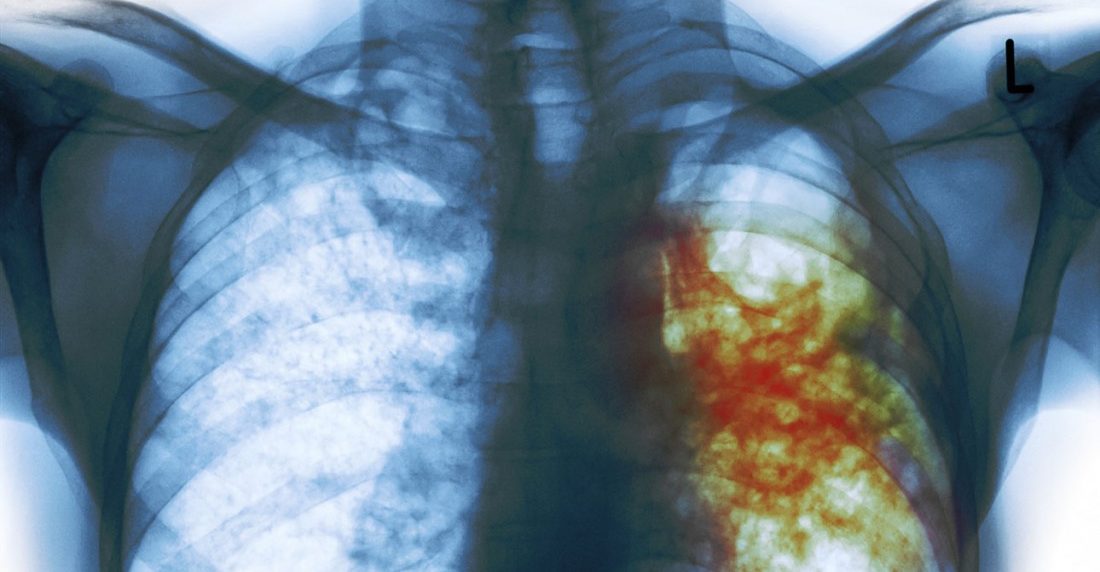

El programa de tuberculosis del Ministerio de Salud proporciona los medicamentos oportunamente a los pacientes, a diferencia de lo que sucede con otras patologías. El sufrimiento, además del producido por la tos crónica, llega cuando se desarrolla una forma grave de la enfermedad y es necesario internarse en un hospital público. Las carencias multiplican el malestar